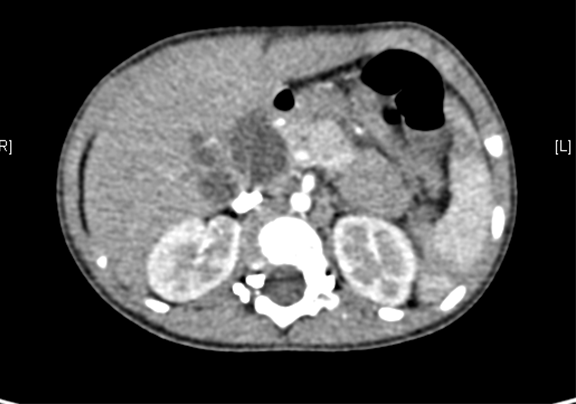

术前CT检查:

动脉期

上腹部动态三维成像(增强)CT:诊断意见:符合胆总管囊肿胆囊炎可能性大。